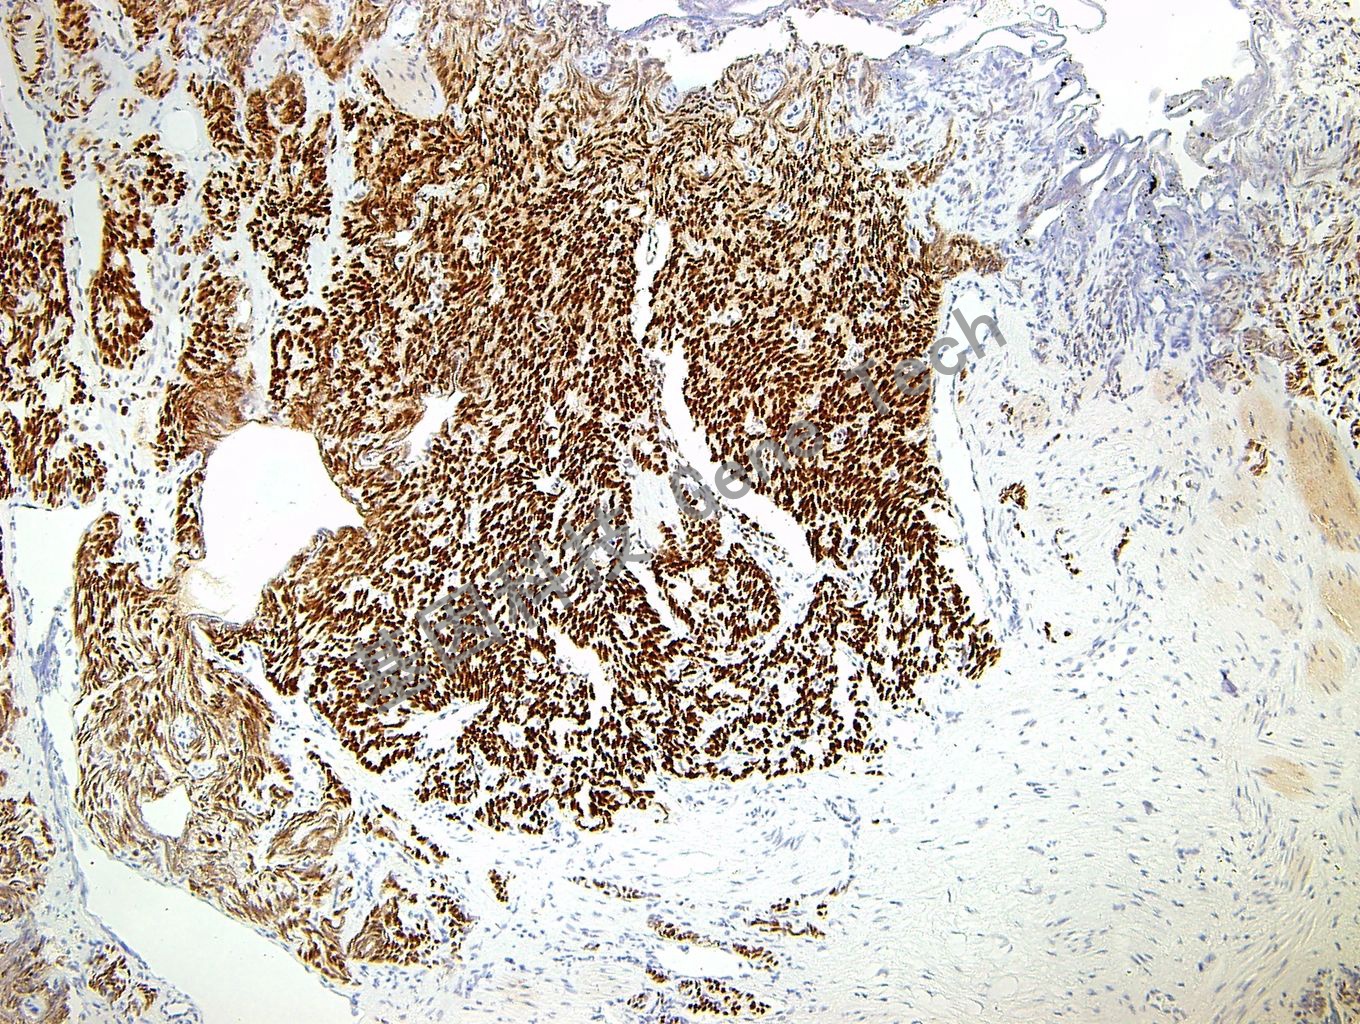

| 預(yù)處理:高pH熱修復(fù) | 陽性部位:細(xì)胞核 | 陽性對照:滑膜肉瘤 |

| 簡介:TLE-1(Transducin like enhancer of split 1, 分裂蛋白1轉(zhuǎn)導(dǎo)蛋白樣增強(qiáng)子) 是TLE基因家族的成員之一,參與造血、神經(jīng)和末端上皮分化。表達(dá)于基底層細(xì)胞、脂肪細(xì)胞、外周神經(jīng)細(xì)胞、內(nèi)皮細(xì)胞及間皮細(xì)胞。在滑膜肉瘤中特異性表達(dá),在神經(jīng)鞘瘤和多形性肉瘤中很少表達(dá)。TLE1在滑膜肉瘤中表達(dá)的敏感性和特異性較Bcl-2 、EMA和CK更高,可作為滑膜肉瘤的標(biāo)記為,用于滑膜肉瘤與其他類型腫瘤的鑒別診斷。 | ||

| 前列腺腺癌石蠟切片,用TLE-1(GT2239)染色,細(xì)胞核陽性,DAB染色 | ||